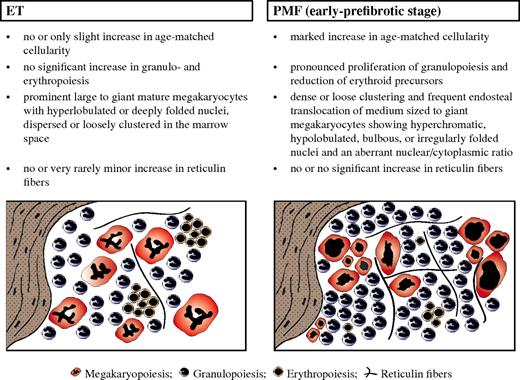

Diagnostic criteria of distinctive value regarding WHO-defined ET (left) versus early-prefibrotic stage of PMF (right), including standardized morphologic features (Table 1 contains more details), allowing the generation of characteristic histologic BM patterns.

Diagnostic criteria of distinctive value regarding WHO-defined ET (left) versus early-prefibrotic stage of PMF (right), including standardized morphologic features (Table 1 contains more details), allowing the generation of characteristic histologic BM patterns.